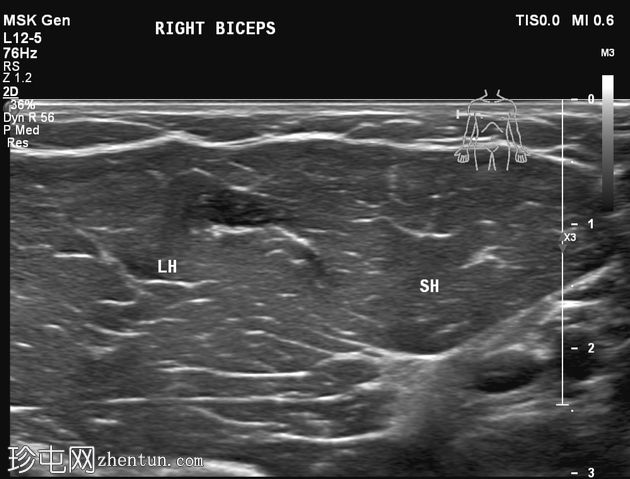

静息状态:肱二头肌短头和长头肌肉结构正常。肌腱和肌腱连接处完整,仅有轻微的断裂或积液迹象。

肘关节屈曲及肌肉收缩动态成像:肱二头肌短头和长头肌纤维之间出现充满液体的裂隙,提示局部肌筋膜分离/拉伤。未见肌纤维全层撕裂。肱二头肌远端止点正常。

诊断:肱二头肌短头和长头之间的动态肌筋膜损伤,收缩时裂隙内积液。

静息状态下的图像可能显示正常,这凸显了对有症状患​​者进行动态检查的重要性。